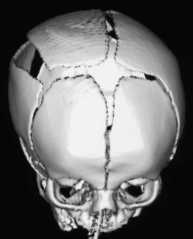

la fracture est le plus souvent pariétale, plus rarement frontale voire orbitaire

lorsque les berges de la fracture sont éloignées de plus de 5 mm, il est hautement probable que la dure-mère sous-jacente soit déchirée

on peut anticiper son développement quand le bilan initial montre unefracture large, une déchirure durale et une contusion sous-jacente

il faut l’évoquer devant une tuméfaction sous-cutanée post-traumatique qui ne se corrige pas (et qu’il faut s’abstenir de ponctionner !)

l’IRM est importante pour évaluer l’extension des lésions cérébrales, la rétraction de la dure-mère, l’existence d’un HSD